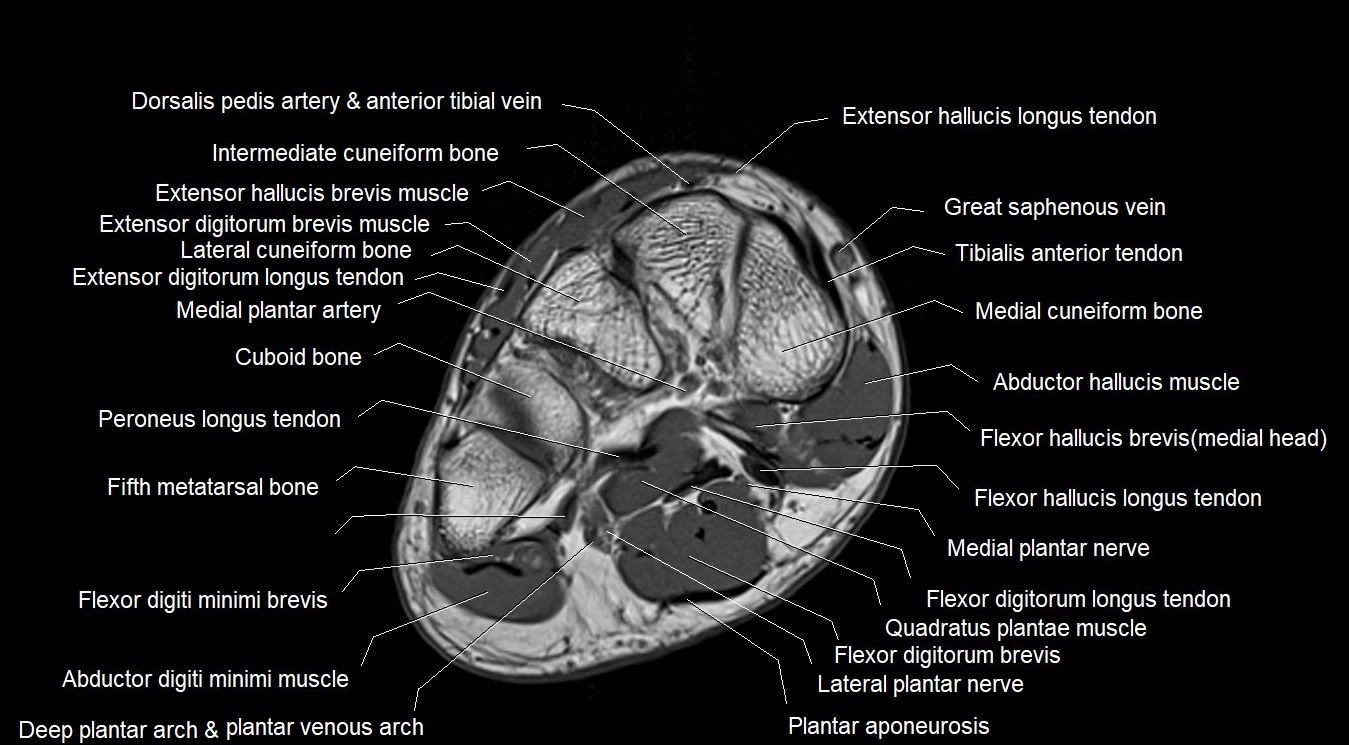

MRI image